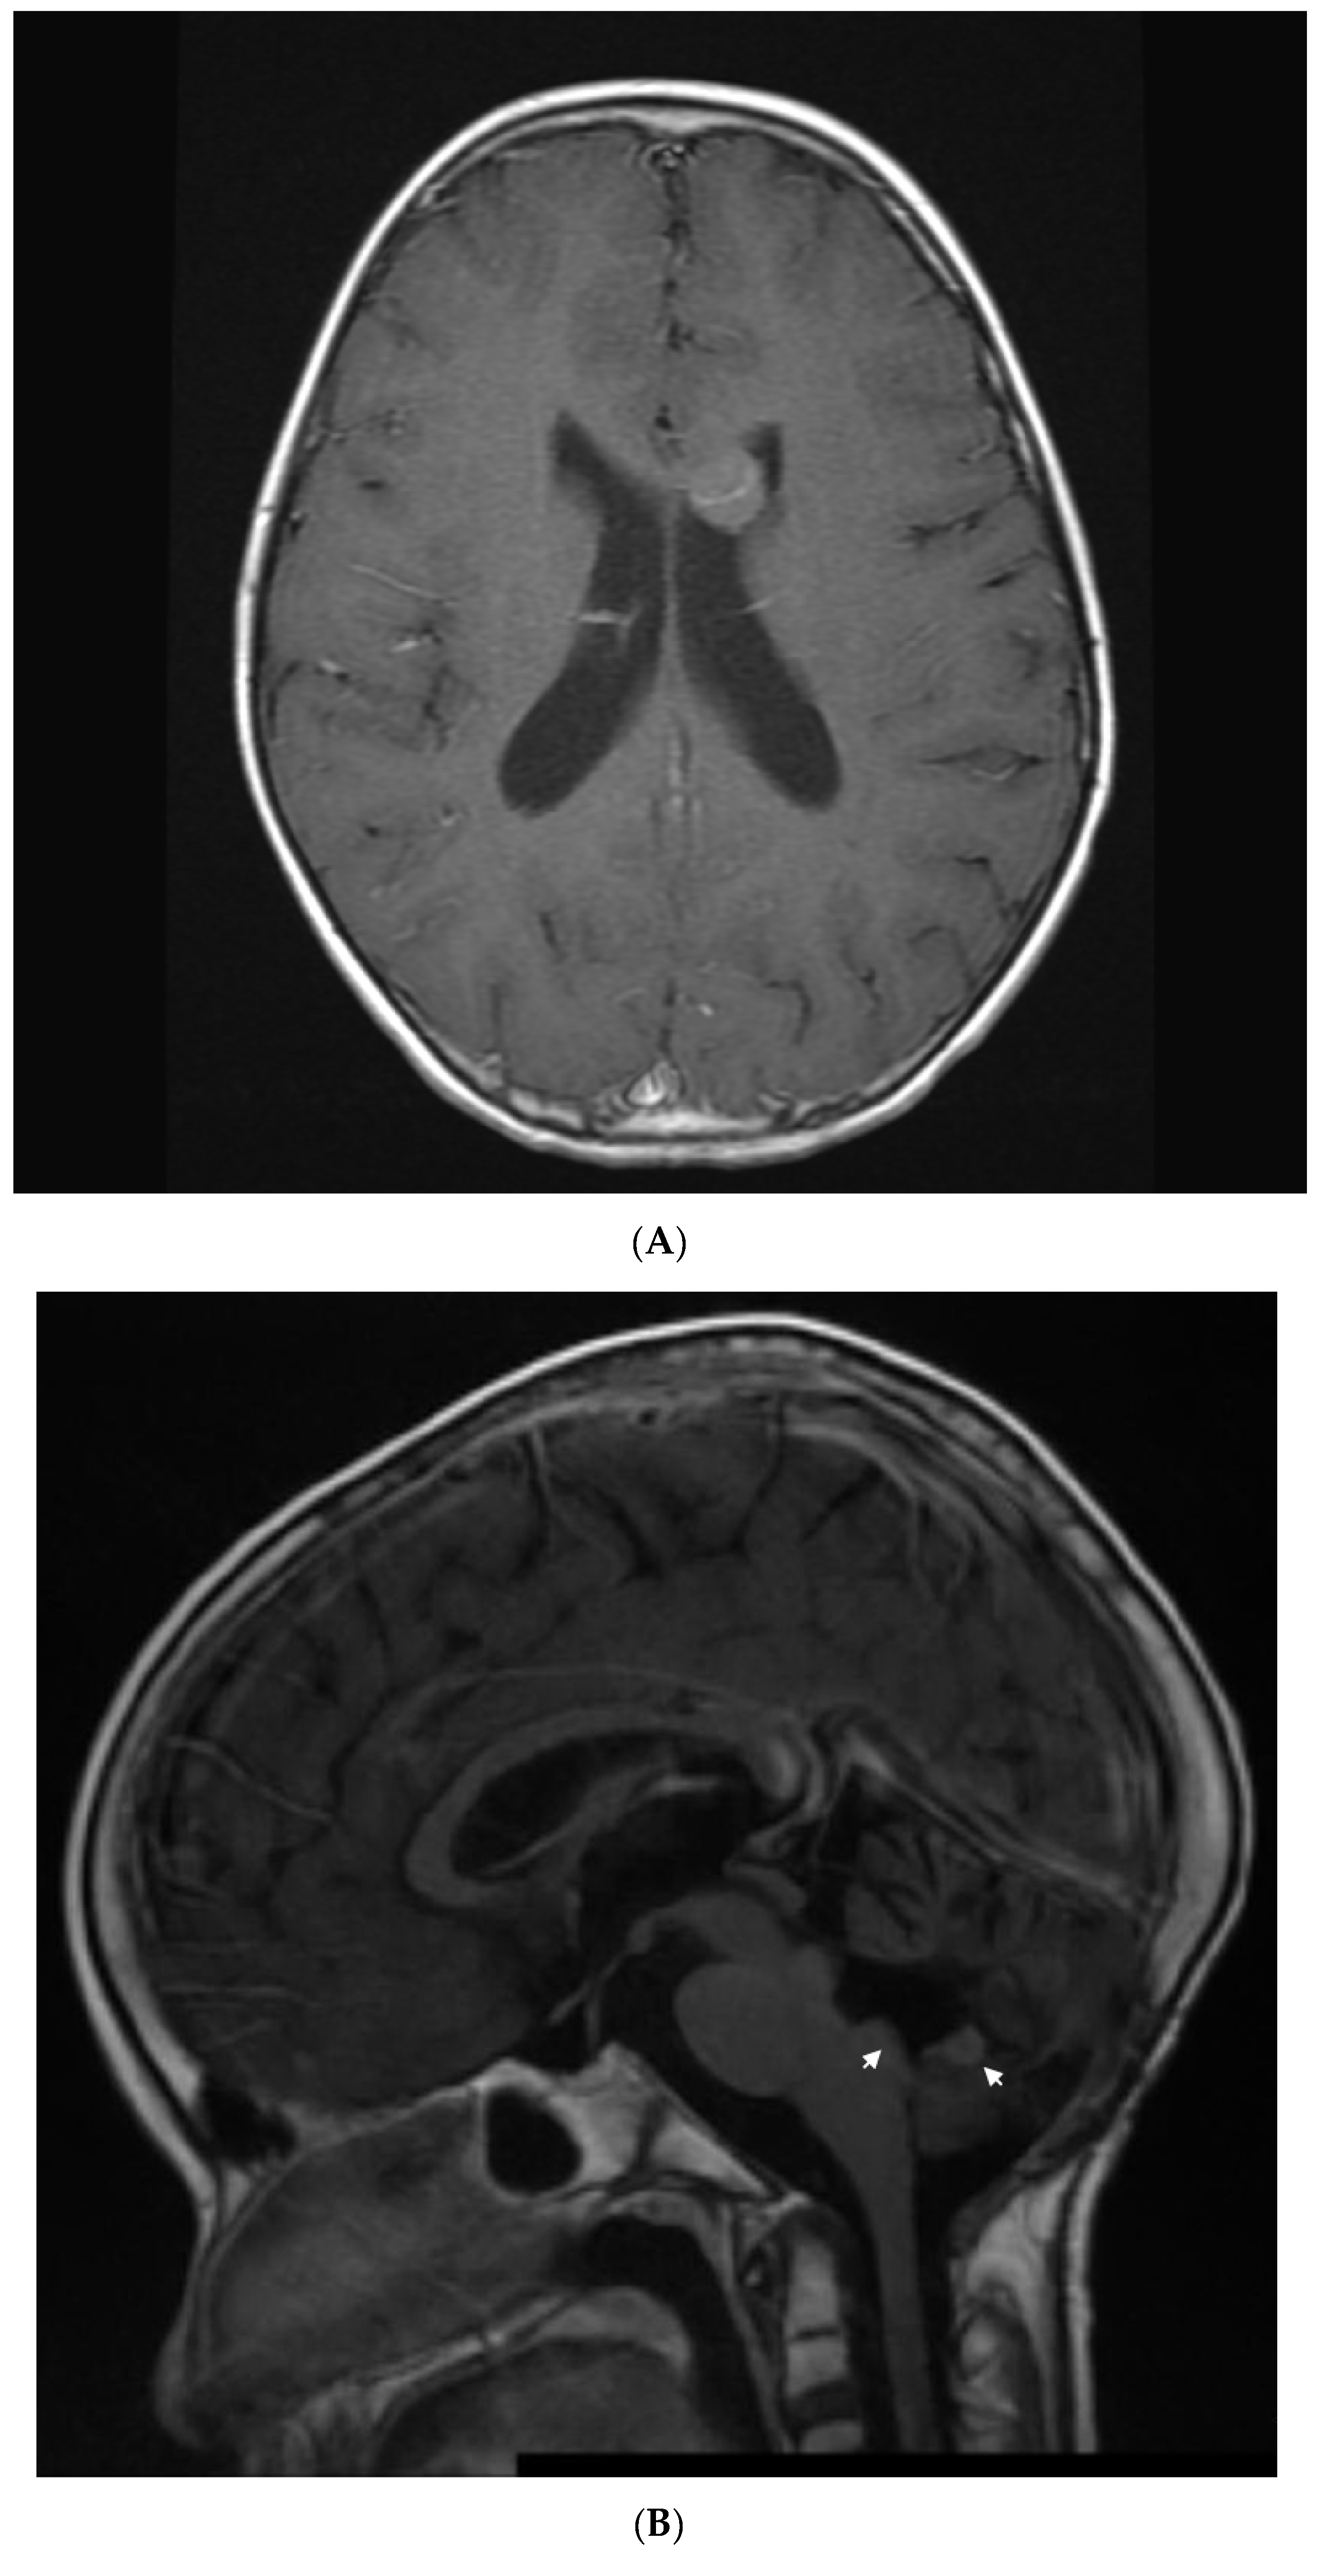

1.2. Patient 2

| 2 | Supratentorial Anaplastic Ependymoma. Local and distant relapse to spine. | VP16-CTX, Celecoxib, VA | 6 years | CR | CR 5.5 years at last encounter Alive 8 years at last encounter |